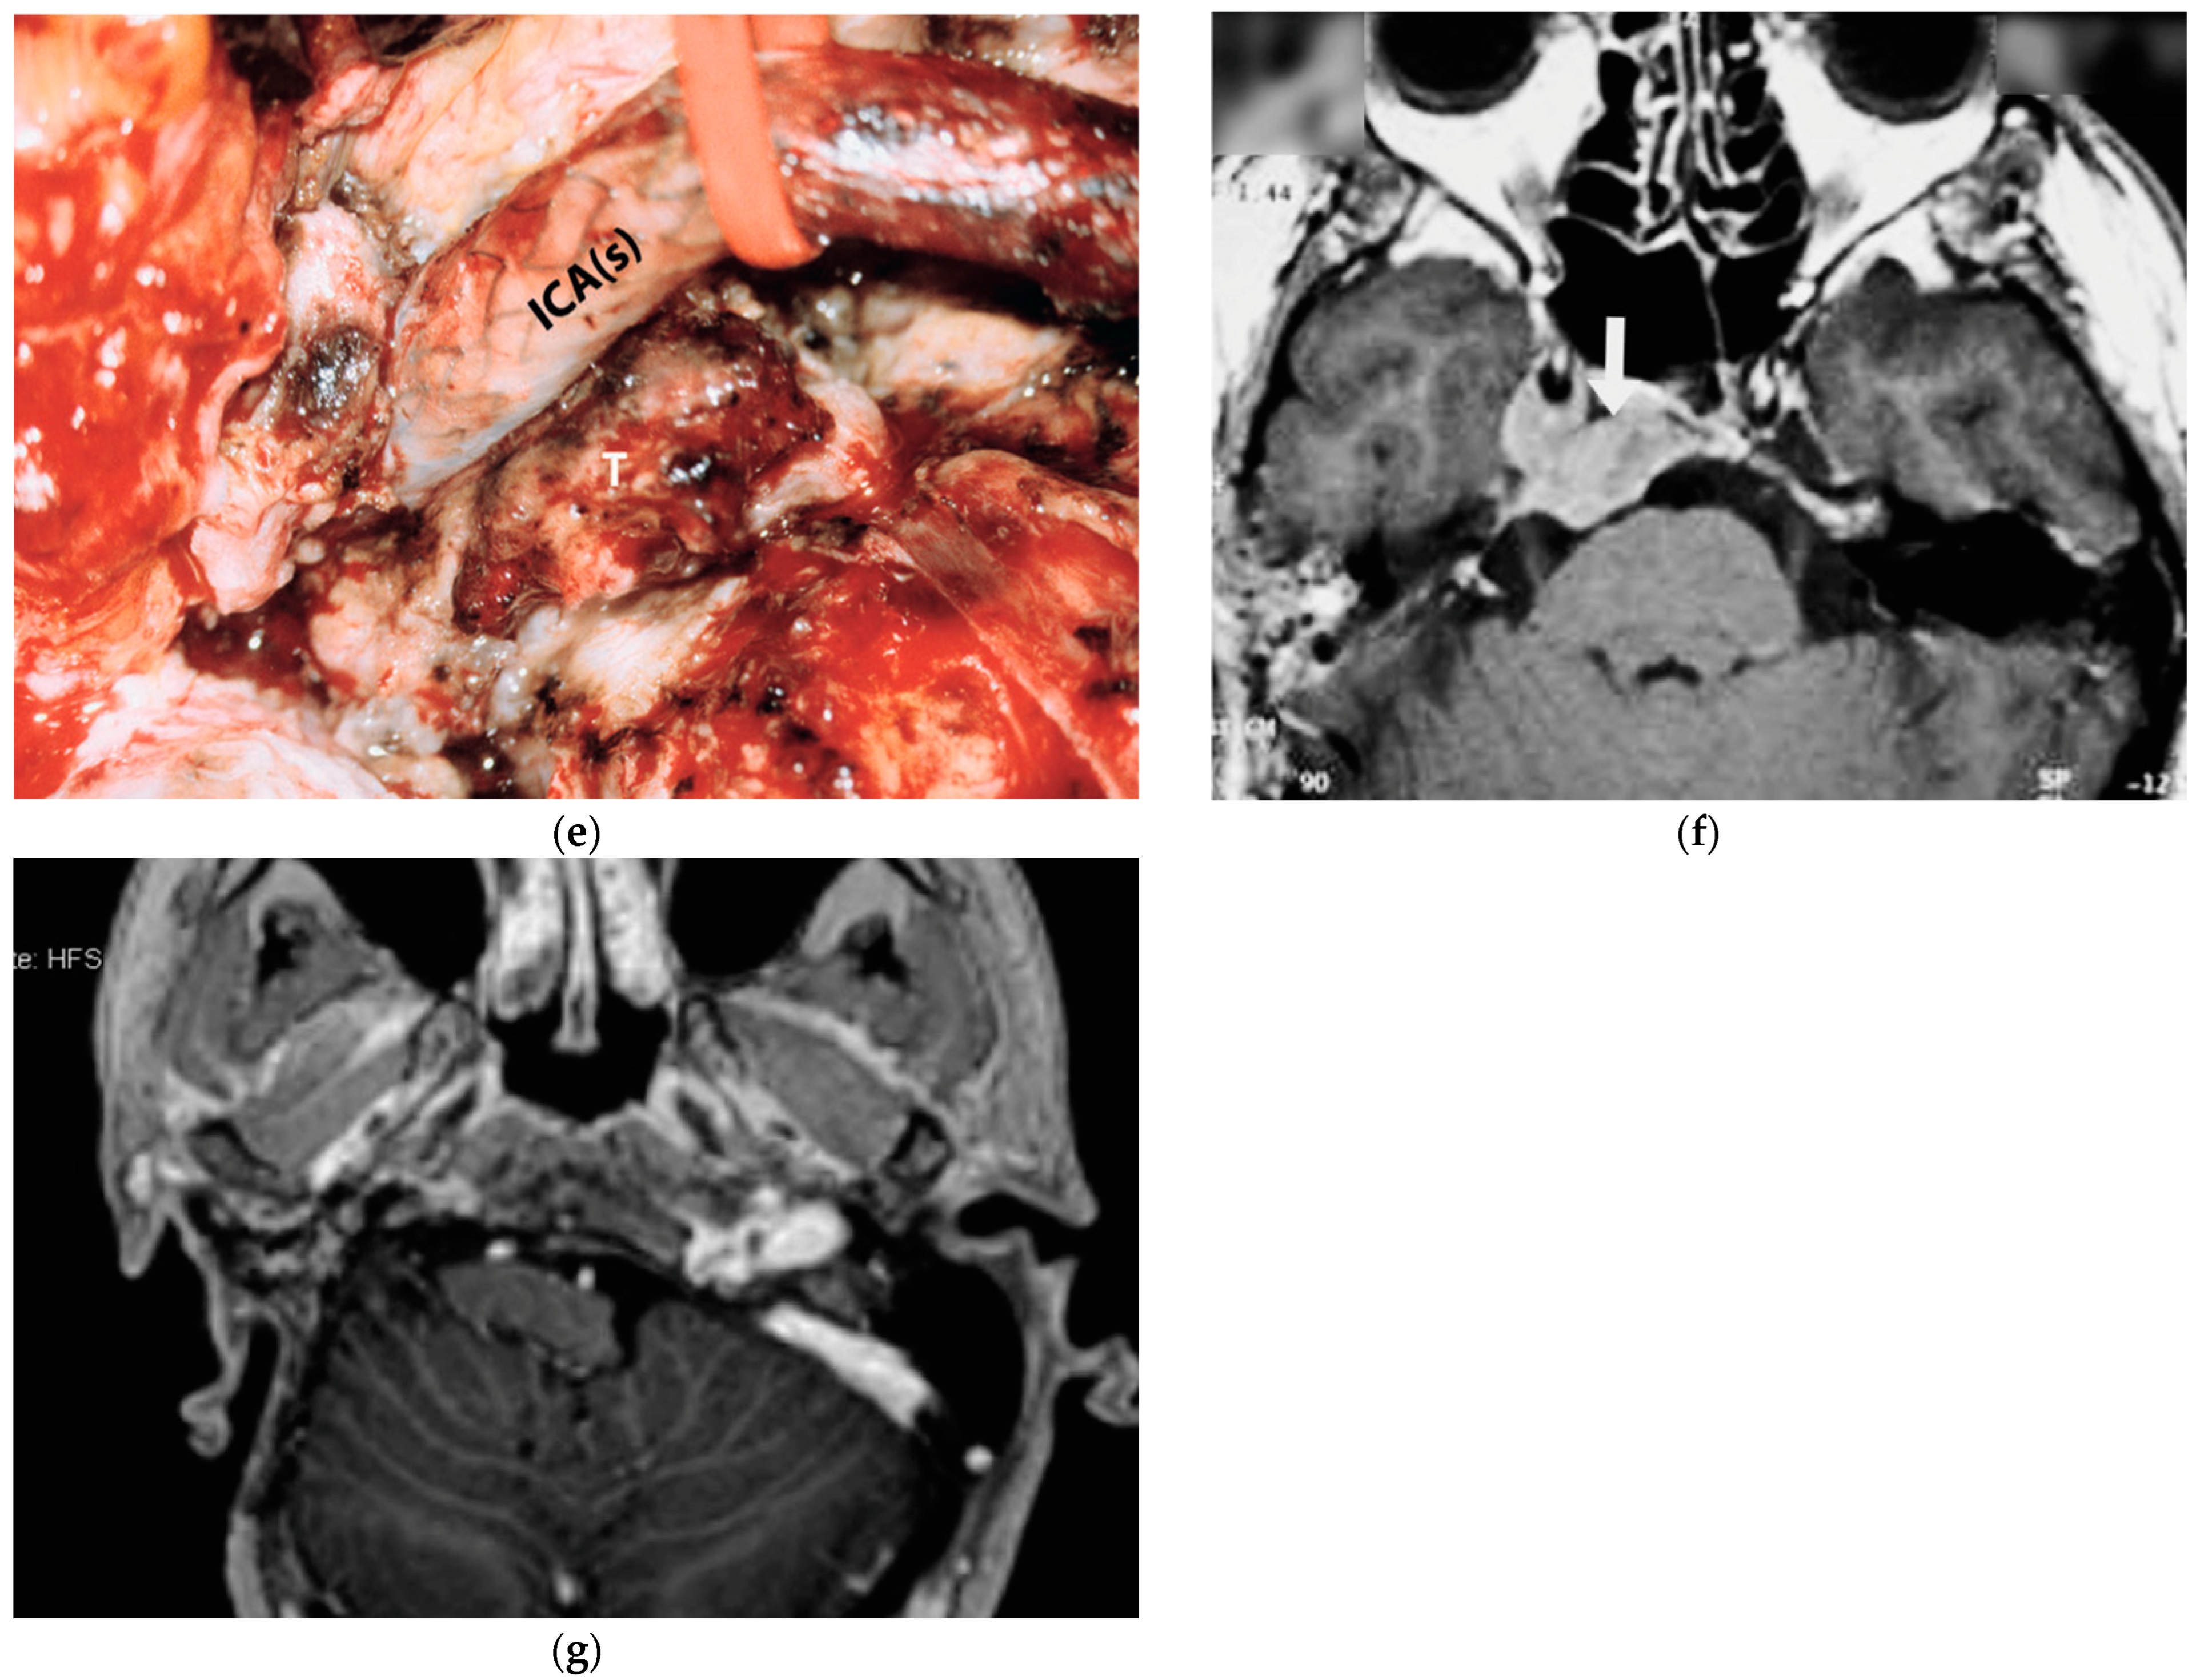

5.5. Case 5: (C3Di2Vi)

5.6. Case 6: (C4Di2Vi)